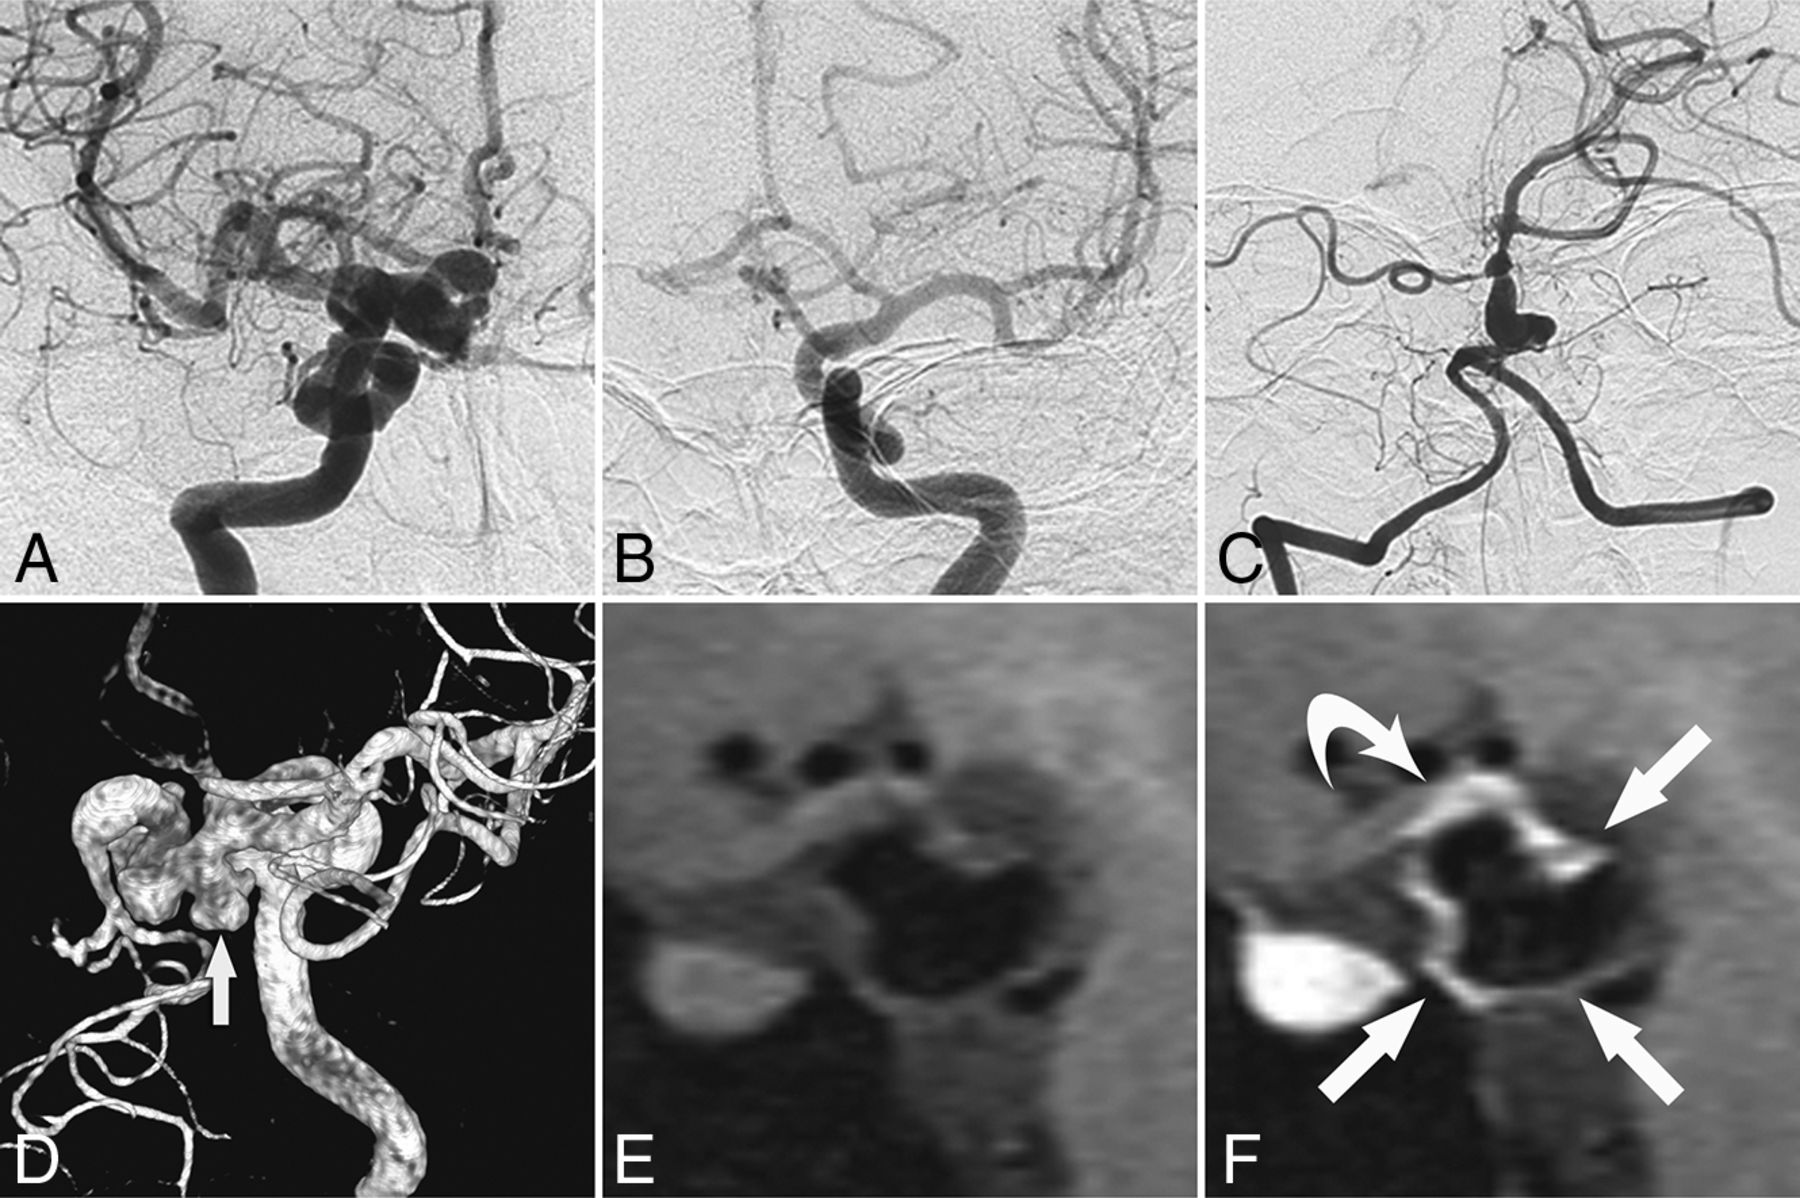

Ten patients underwent contrast-enhanced high-resolution MR imaging of the vessel wall, which detected enhancement in 6 patients with a mean age of 22.8 ± 13.2 years; the remaining 4 patients had a mean age of 57.0 ± 9.2 years (P < .001). One patient (patient 1, Fig 3) exhibited vessel wall enhancement at both 8 and 12 years of age, with no major change in the enhancement pattern. Vessel wall imaging revealed that the stenotic segment exhibited either an eccentric or concentric wall thickening (Fig 4) as well as a potential enhancement of the parent artery and aneurysm neck (Fig 5).

Evolution of vessel wall enhancement with aging in a patient with PHACE syndrome (patient 1, an 8-year-old girl). A and B, Left ICA angiography (anteroposterior and oblique views) reveals tortuosity in the left distal ICA with a small and long A1 segment. C and D, Noncontrast and contrast-enhanced vessel wall imaging at 8 years of age demonstrates vessel wall enhancement and slight vessel wall thickening (arrow in D). E and F, Vessel wall imaging at 12 years of age shows a similar vessel wall enhancement pattern (arrow in F).

Vessel wall enhancement at the stenotic segment in a patient with possible PHACE syndrome (patient 5, a 23-year-old woman). A and B, Left ICA angiography and TOF-MRA reveal dolichoectasia of the left distal ICA, left PcomA (arrow), and left AchoA (curved arrow). C–E, Section images reveal the vessel wall thickening and enhancing patterns of each corresponding stenotic segment (arrowheads indicate the vessel wall thickening and asterisks indicate vessel lumen; C, sagittal plane; D and E, axial plane). P indicates posterior; R, right.

Vessel wall enhancement at the aneurysm wall and the parent artery wall in a patient without PHACE syndrome (patient 11, a 45-year-old woman). A–C, Cerebral angiography shows dolichoectasia in the right distal ICA and basilar artery. D, 3D-DSA shows dolichoectasia in the right distal ICA and right PcomA as well as the formation of multiple aneurysms in the right PcomA (arrow). E and F, Non-contrast-enhanced and contrast-enhanced vessel wall imaging shows enhancement of the aneurysm wall (arrows in F) and the parent artery wall (curved arrow in F).